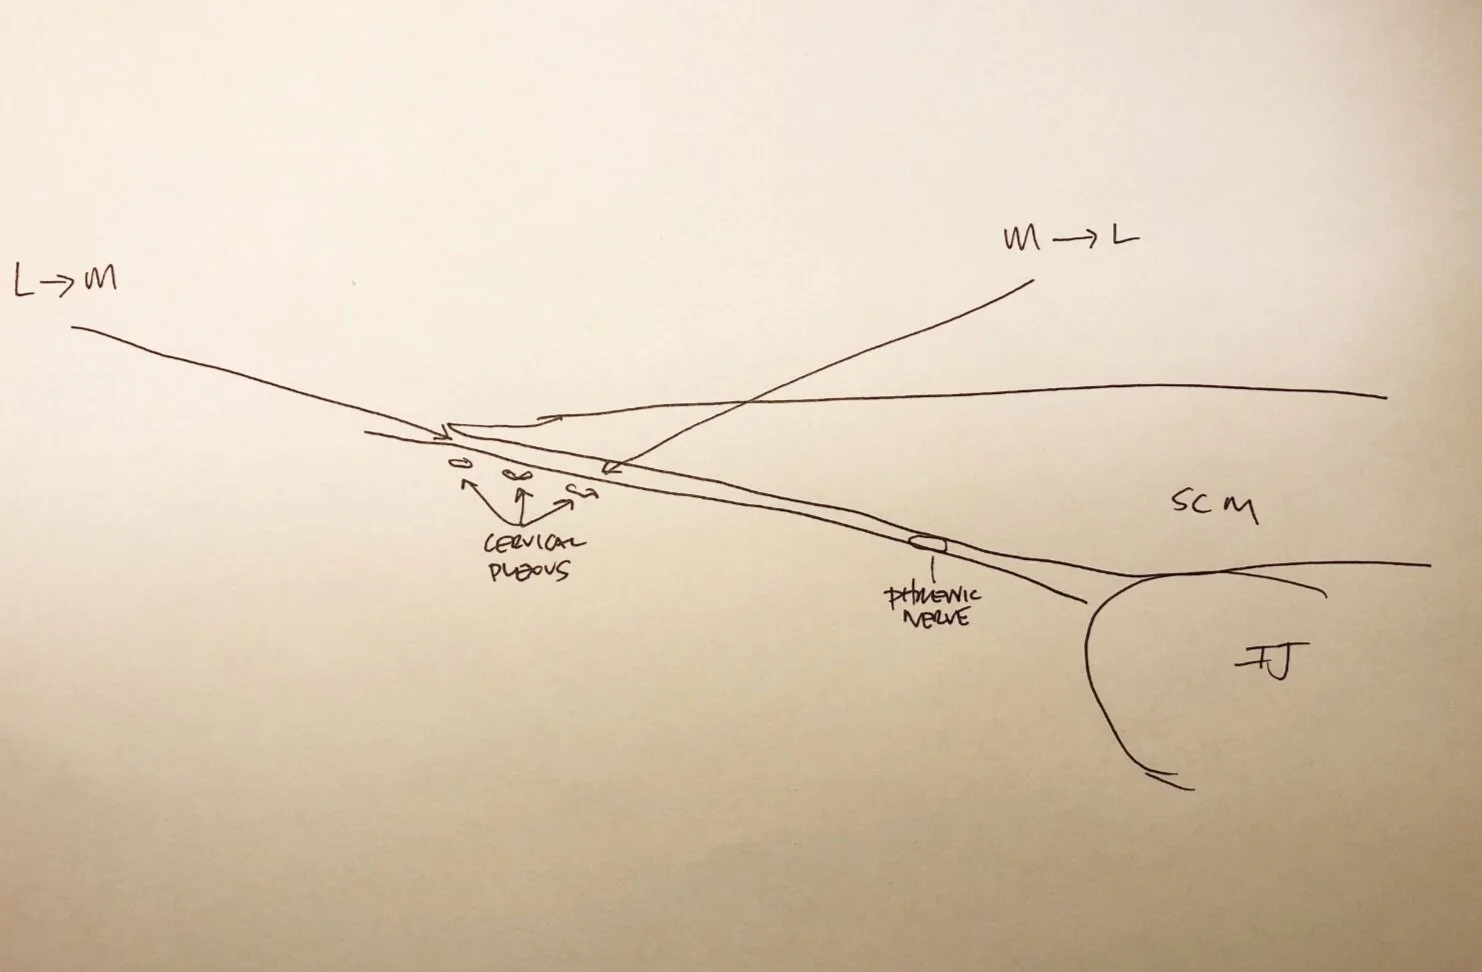

Ultrasound: In-plane approach

After sterile prep, place probe on the ipsilateral neck at level of cricoid cartilage (C6, roughly the middle of the SCM muscle)

Moving the probe from medial to lateral, trace the SCM as it tapers laterally. If having trouble, first locate the great vessels. The SCM lies anteriorly.

If possible, identify the cervical plexus deep and posterolateral to the lateral edge of the SCM muscle as a hypoechoic collection of nodules. If not identifiable, LA can be deposited beneath the lateral edge of the SCM and prevertebral fascia. If in the correct plane, the LA will 'unzip' the layers similar to a TAP or rectus sheath block. Adjust needle tip accordingly to achieve this view. The phrenic nerve is routinely in this fascial plane (though deeper and medial), so ensure LA spread is more lateral and superficial to avoid unintentional phrenic nerve block.